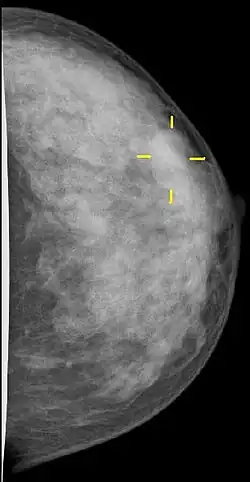

Najczęściej używa się amerykańskiego systemu BI-RADS[67]. Określa on stopień złośliwości zmian w skali cyfrowej (0: wynik niejednoznaczny, 1: wynik negatywny itd. aż do 6: wynik pozytywny, potwierdzony hist-pat.). Cenną informacją jest też ocena „gęstości piersi”, parametr rzutujący na czułość mammografii (A: wyłącznie tkanka tłuszczowa, dobra czułość badania; D: pierś „gęsta” z dużą zawartością tkanki gruczołowej oraz włóknistej, czułość niedostateczna). W podobny sposób można definiować wyniki badania ultrasonograficznego piersi, MRI itp.

Rozpoznanie wspomagane komputerowo

Wraz z postępującą digitalizacją badań radiologicznych (skanowanie negatywów, detektory cyfrowe) wzrosła szansa na opracowanie wydajnych aplikacji wykrywających zmiany nowotworowe. Na chwilę obecną takie rozpoznanie wspomagane komputerowo (ang. computer-aided detection, CAD) nie jest metodą całkowicie wiarygodną[70], ale rozwój algorytmów odbywa się niezwykle dynamicznie. Według niektórych potrafią one już w tej chwili zastąpić konsultację z drugim radiologiem[71], ale często większa czułość odbywa się kosztem wzrostu ilości rozpoznań fałszywie pozytywnych[72]